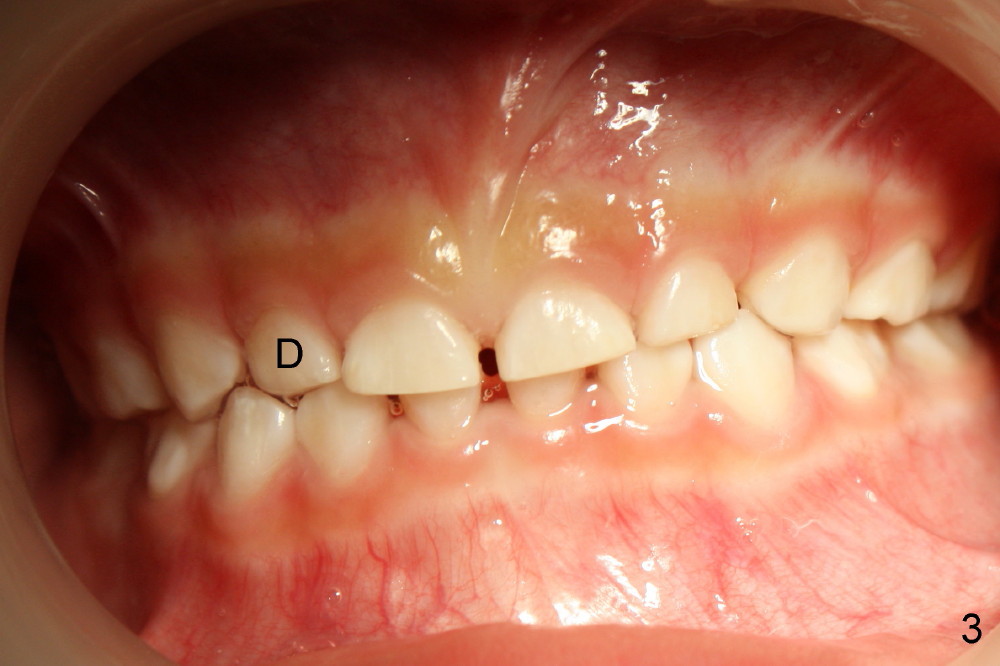

Devon's 9-year-old sister has basically normal tooth alignment, whereas 4-year-old sister has single-tooth cross bite (Fig.3 D, deciduous lateral incisor). Other than that, the younger sister is fine (Fig1, upper occlusal) with normal spacing between deciduous teeth (Fig.2 (lower occlusal): *).

Devon(男孩)的姐姐(九岁)牙齿基本整齐,四岁妹妹有轻度不齐,例如右上乳侧切牙反合(图三:D),除此之外,发育正常,例如出现乳牙间隙(图二:*)。